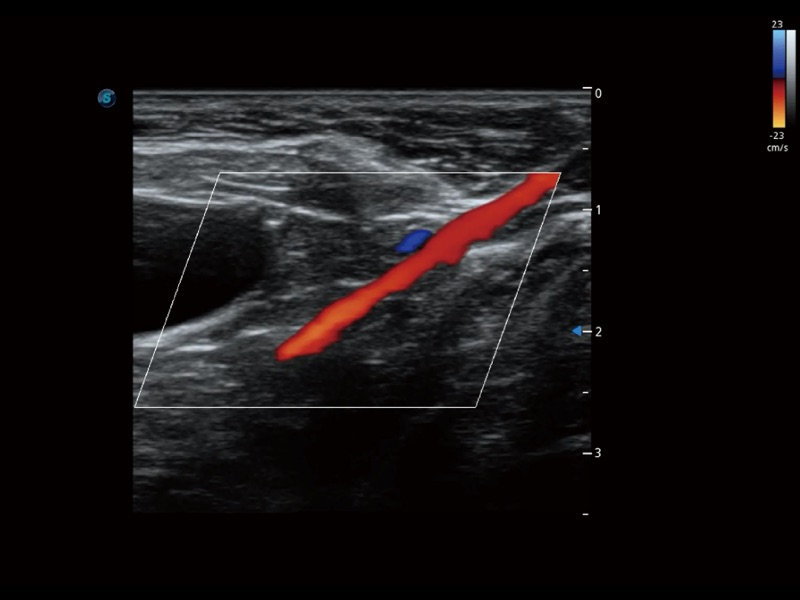

增强穿刺针在动物解剖结构中的位置,提高穿刺介入的安全性和准确性。

通过色彩血流和实时宽景相结合,可观察到完整的静脉或动脉的血流,方便医生检查。实时扫查过程中,如有任何操作失误也可以很容易地进行回扫擦除,而不会中断扫查。